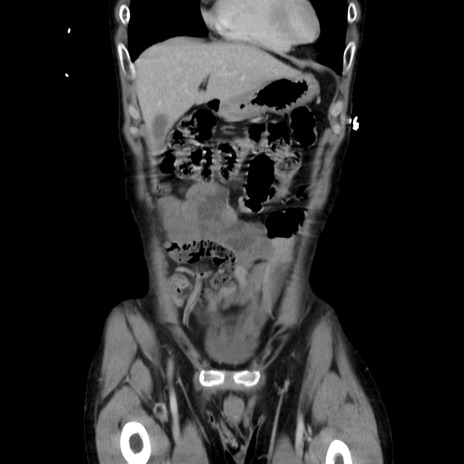

症例37(冠状断像)

【症例】40歳代 男性

【主訴】腹痛

【現病歴】4時間ほど前に電車に乗車中に臍部上より腹痛出現。徐々に増悪し起立困難となり、救急外来受診。生ものは数日食べていない。今朝お雑煮を食べた。

【身体所見】BT 36.8℃、BP 117/84mmHg、HR 91/min、SpO2 97%、苦悶様、腹部:臍上部広範囲圧痛あり、反跳痛±

【データ】WBC 8100、CRP 0.03